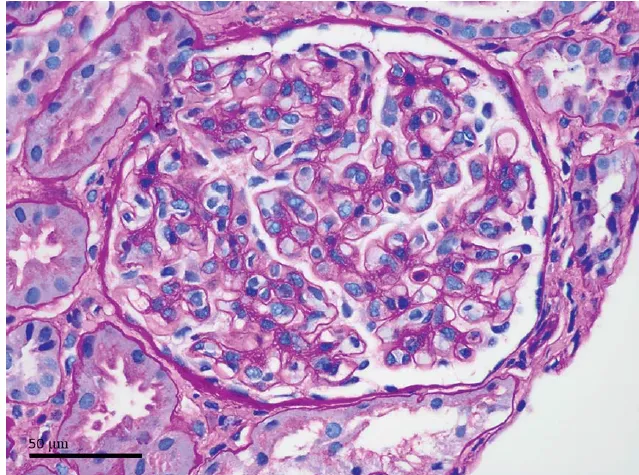

Na urina, a relação proteína/creatinina foi de 169 mg/g. O exame de urina automatizado mostrou: pH 5,0, densidade 1,009, sangue +++, esterase leucocitária, glicose, proteínas e nitritos negativos. O sedimento urinário automatizado mostrou 50 – 100 RBC/HPF (sem dismorfismo) e cristais de ácido úrico +.

Devido à persistência da cristalúria de ácido úrico, foi solicitada uma revisão manual do sedimento urinário por um observador experiente, que identificou a seguinte imagem:

Na análise urinária os cristais apresentavam formato esférico irregular e estrias radiais, coloração amarela a marrom e forte birrefringência positiva. Com suspeita clínica de IRA associada a cristais de SMX, foi realizada a alcalinização da urina com bicarbonato de sódio. O paciente respondeu favoravelmente, com resolução completa da IRA.